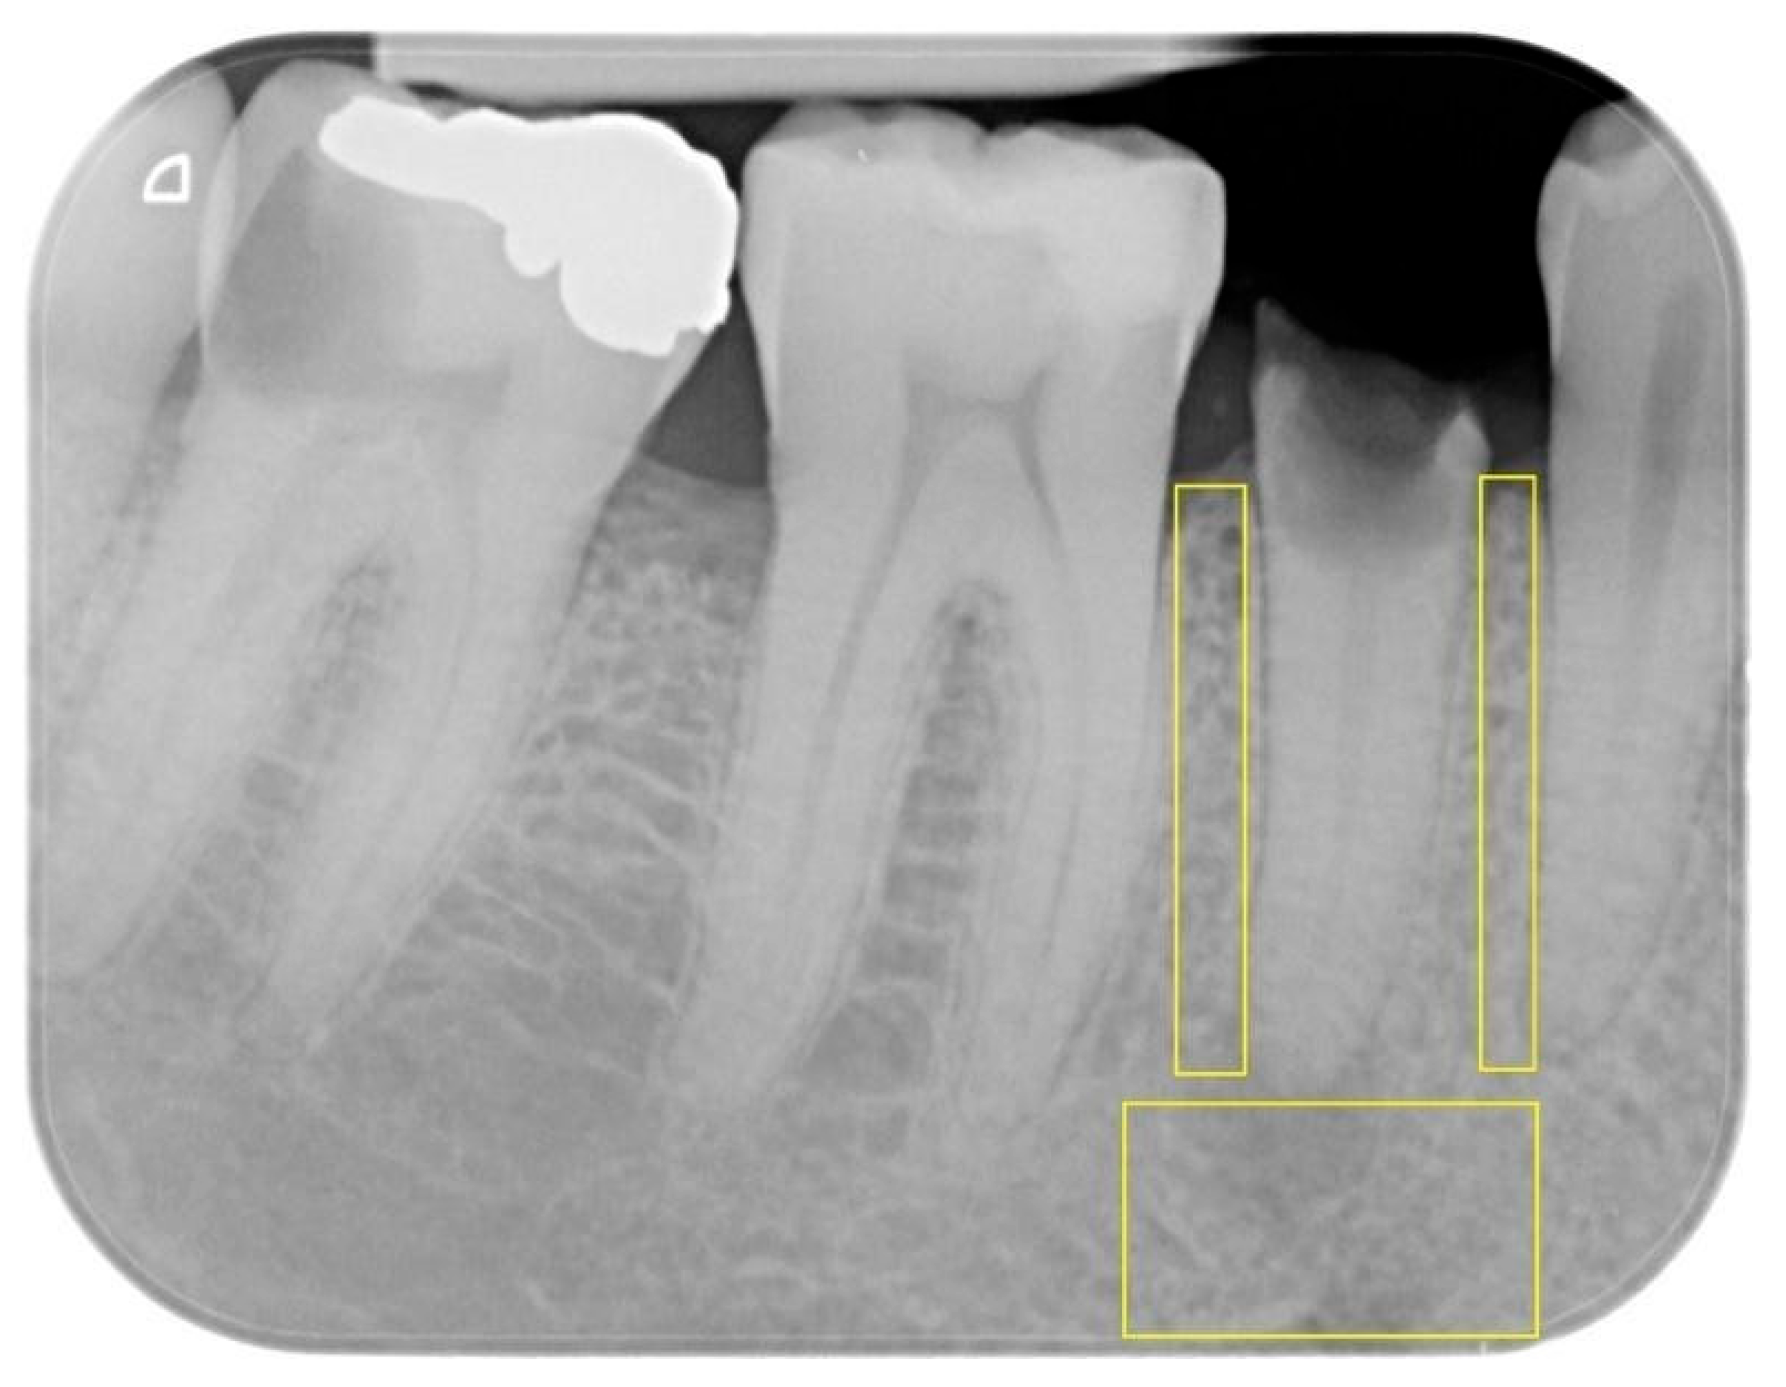

- Apical ROI: extending horizontally between the mesial and distal root surfaces of the tooth and vertically between the root apex and the lower edge of the image.

- Mesial proximal ROI: extending vertically from the mesial alveolar ridge to the tooth apex and horizontally between the root surfaces of the two adjacent teeth.

- Distal proximal ROI: extending vertically from the distal alveolar ridge to the tooth apex and horizontally between the root surfaces of the two adjacent teeth.